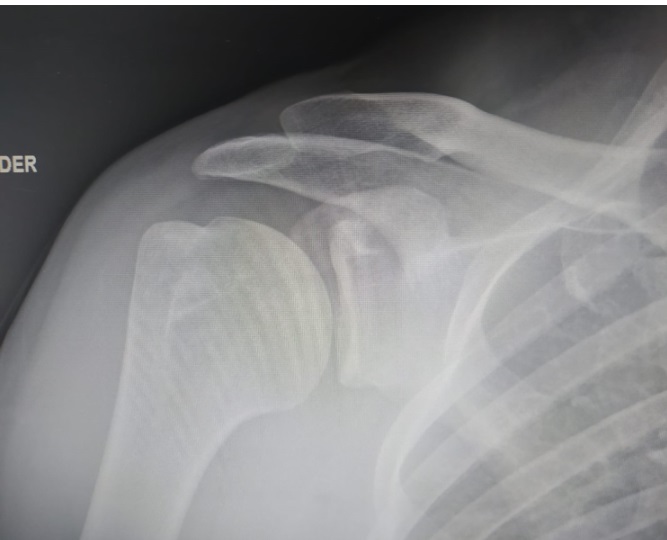

• Se realizó una radiografía de hombro, donde no se encontraron alteraciones.